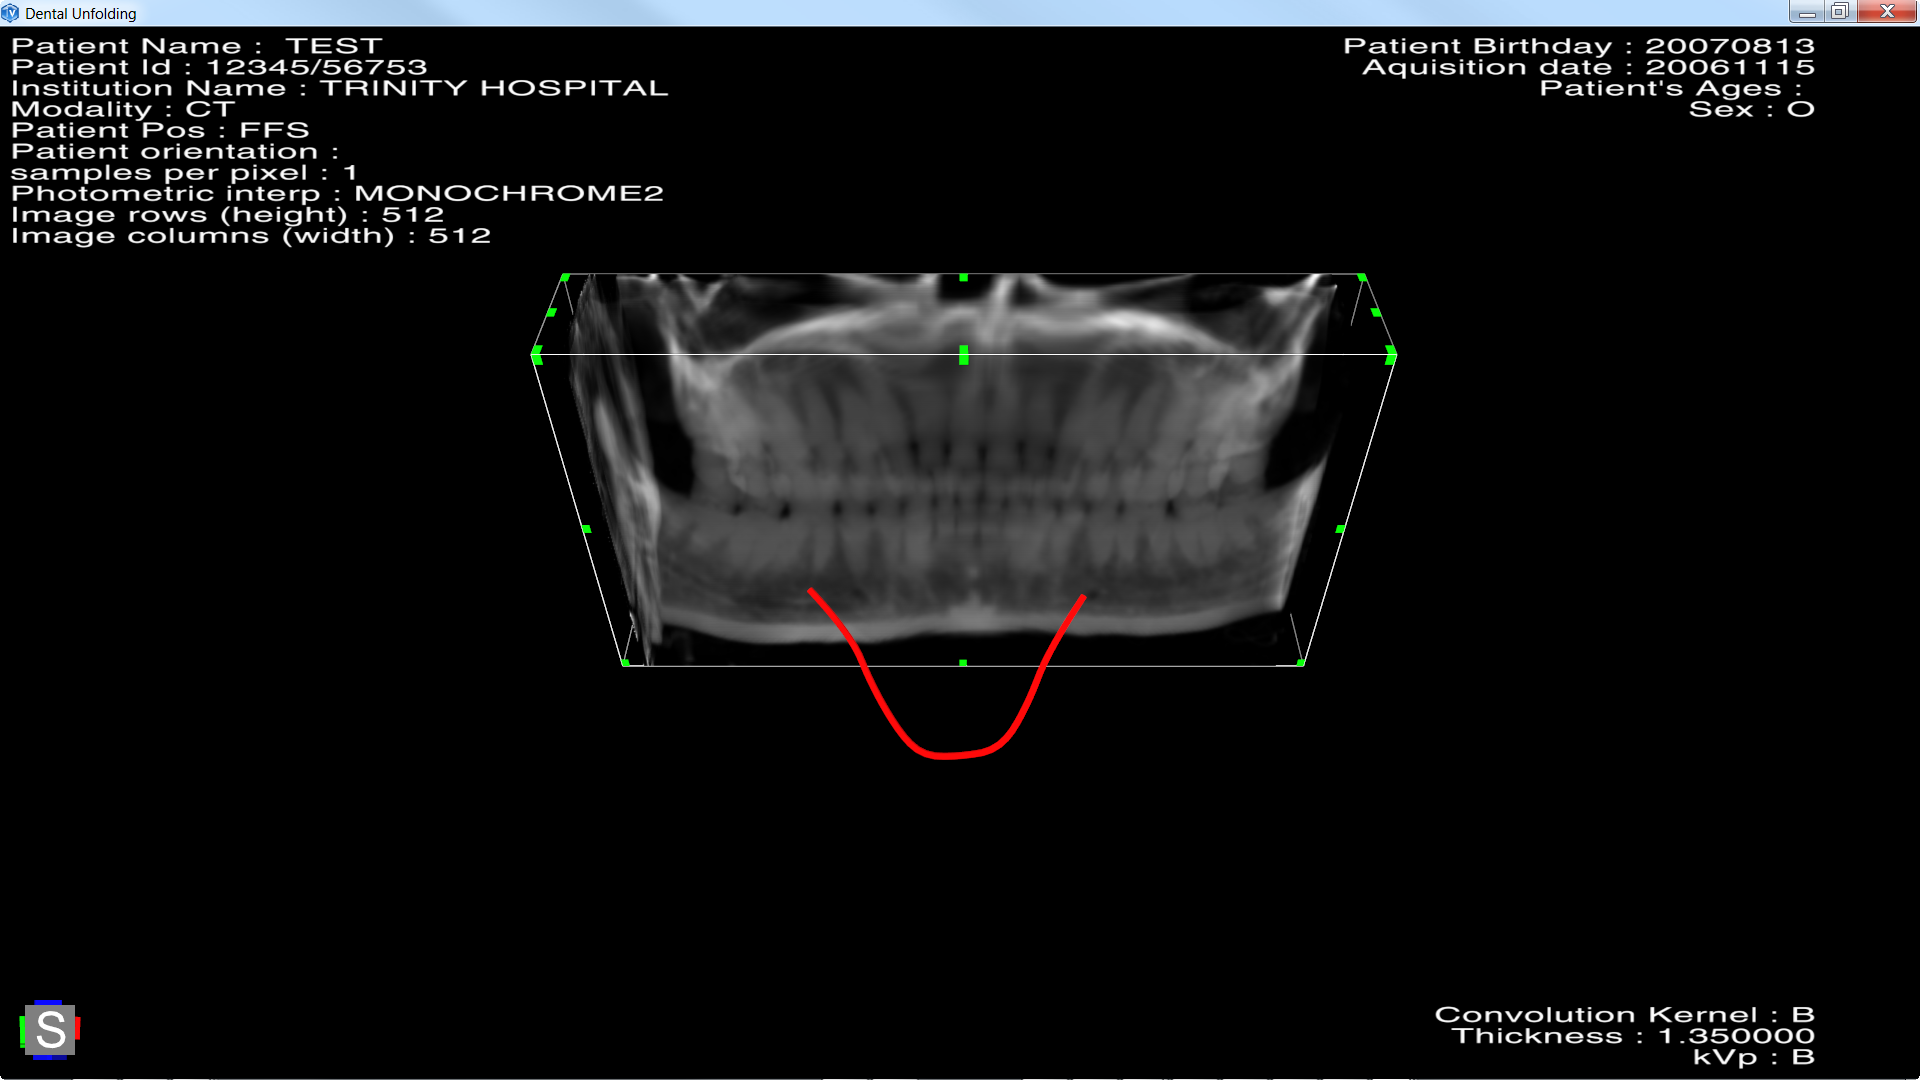

SCREENSHOT:

Before unfolding, the red spline define the path to follow for the unfolding.